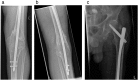

Bone healing is a complex and well-orchestrated physiological process, in which bone repairs and regenerates regaining its original biomechanical and biochemical properties. It is estimated that 5 to 10% of all fractures are complicated by delayed union or non-union. Progression to non-union is thought to be multifactorial, even though the exact biological sequence remains obscure. Treatment should aim to addressing deficiencies in both the mechanical and biological components, along with eliminating co-factors that could negatively affect the locally induced fracture healing response. We report a case of a 78-year-old patient who presented with a distal femoral non-union above a previously fused knee, which was successfully managed with exchange nailing and intramedullary delivery of recombinant human bone morphogenetic protein-7 (rhBMP-7).